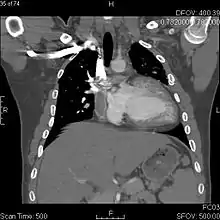

![]() Fontan procedure for tricuspid atresia | |

The Fontan procedure or Fontan–Kreutzer procedure is a palliative surgical procedure used in children with univentricular hearts. It involves diverting the venous blood from the inferior vena cava (IVC) and superior vena cava (SVC) to the pulmonary arteries. The procedure varies for differing congenital heart pathologies. For example in tricuspid atresia, the procedure can be done where the blood does not pass through the morphologic right ventricle; i.e., the systemic and pulmonary circulations are placed in series with the functional single ventricle. Whereas in hypoplastic left heart syndrome, the heart is more reliant on the more functional right ventricle to provide blood flow to the systemic circulation. The procedure was initially performed in 1968 by Francis Fontan and Eugene Baudet from Bordeaux, France, published in 1971, simultaneously described in 1971 by Guillermo Kreutzer from Buenos Aires, Argentina, and finally published in 1973.[1][2]